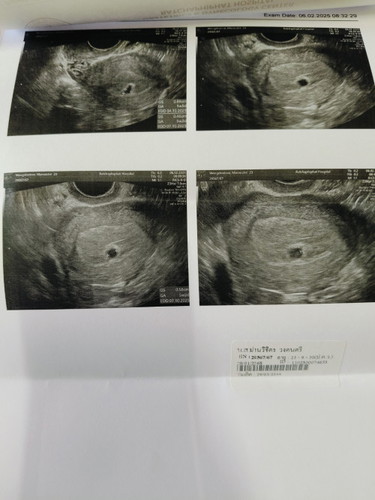

สอบถามแม่ๆหน่อยค่ะ มีเลือดออกที่ช่องคลอด เป็นลิ่มๆ เวลาปัสสาวะเลือดจะไหลมาพร้อมฉี่ค่ะ วันนี้เลยได้ไปหาคุณหมอ หมออัลตร้าซาวด์ไห้ทางช่องคลอดเจอแต่ถุงตั้งครรภ์ยังไม่เจอตัวอ่อนเลยค่ะ คุณหมอบอกเสี่ยงแท้ง50-50 หรือไม่อาจจะท้องลมได้ค่ะ อีก2อาทิยต์คุณหมดนัดไปอัลตร้าซาวด์อีกครั้งค่ะ แม่พอจะมีสิทธิ์เจอตัวน้องไหมค่ะแบบนี้😭😭😭